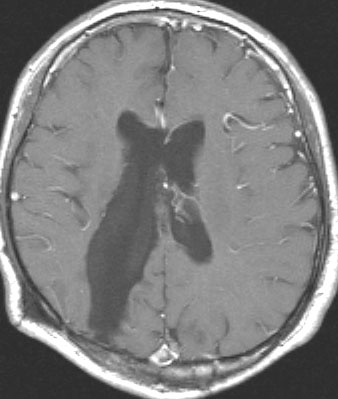

20代の男性の神経細胞腫です。側脳室の中のとても大きな腫瘍です。上段はガドリニウムという造影剤を入れた時のMRIです。下段の中央はCTですが,石灰化が見られます。脳外科の先生には,この脳室内腫瘍は一見transcallosal approach(経脳梁到達法)という手術で取れるように見えるかもしれませんが,そうではなくて,脳室の壁とくに上壁と側壁にくっついているのでなかなか取れません。この患者さんの場合は右の頭頂葉というところからtranscortical approach(経皮質到達法)で全摘出しました。後遺症もなく再発もなく術後10年が過ぎています。全部とれれば治ってしまう腫瘍です。